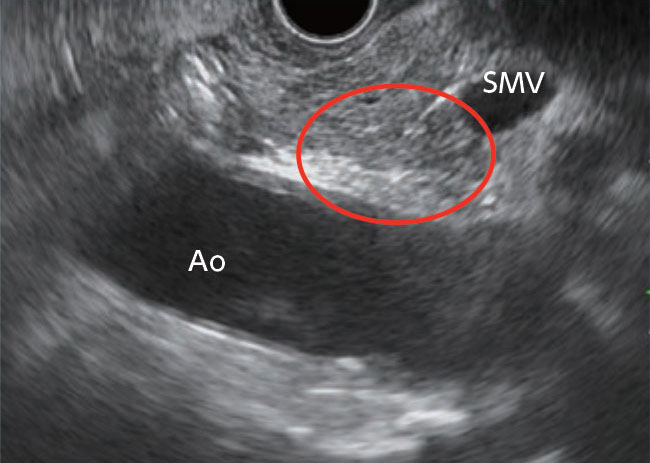

To observe the entire head of the pancreas without missing anything, it is necessary that you understand the anatomical positioning of the uncinate process of the pancreas and carefully observe it and the surrounding area. From the descending part of the duodenum, you can recognize the area of the uncinate process of the pancreas by first visualizing the superior mesenteric vein and the head of the pancreas and then turning the scope counterclockwise from there to observe the aortic side. On the other hand, if you have observed the head of the pancreas by visualizing the aorta in the long axis direction while withdrawing the scope, you can image the area of the uncinate process of the pancreas by turning the scope clockwise from there (Fig., circled section).

Fig.